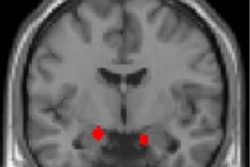

Functional MRI highlights two brain regions where veterans trained in mindfulness saw the greatest increases in connections. Image courtesy of the University of Michigan/VA Ann Arbor.Even when they were asked to rest quietly and let their minds wander freely, the patients had high levels of activity in brain networks that control reactions to external signals, such as threats or dangers. Meanwhile, the default mode network (DMN), involved in inwardly focused thinking and when the mind is wandering, was not as active.

Most interestingly, the researchers were able to track the improvement in the mindfulness group on fMRI. Those who received mindfulness training developed stronger connections between two brain networks: one associated with inner, sometimes meandering thoughts, and another involved in shifting and directing attention.